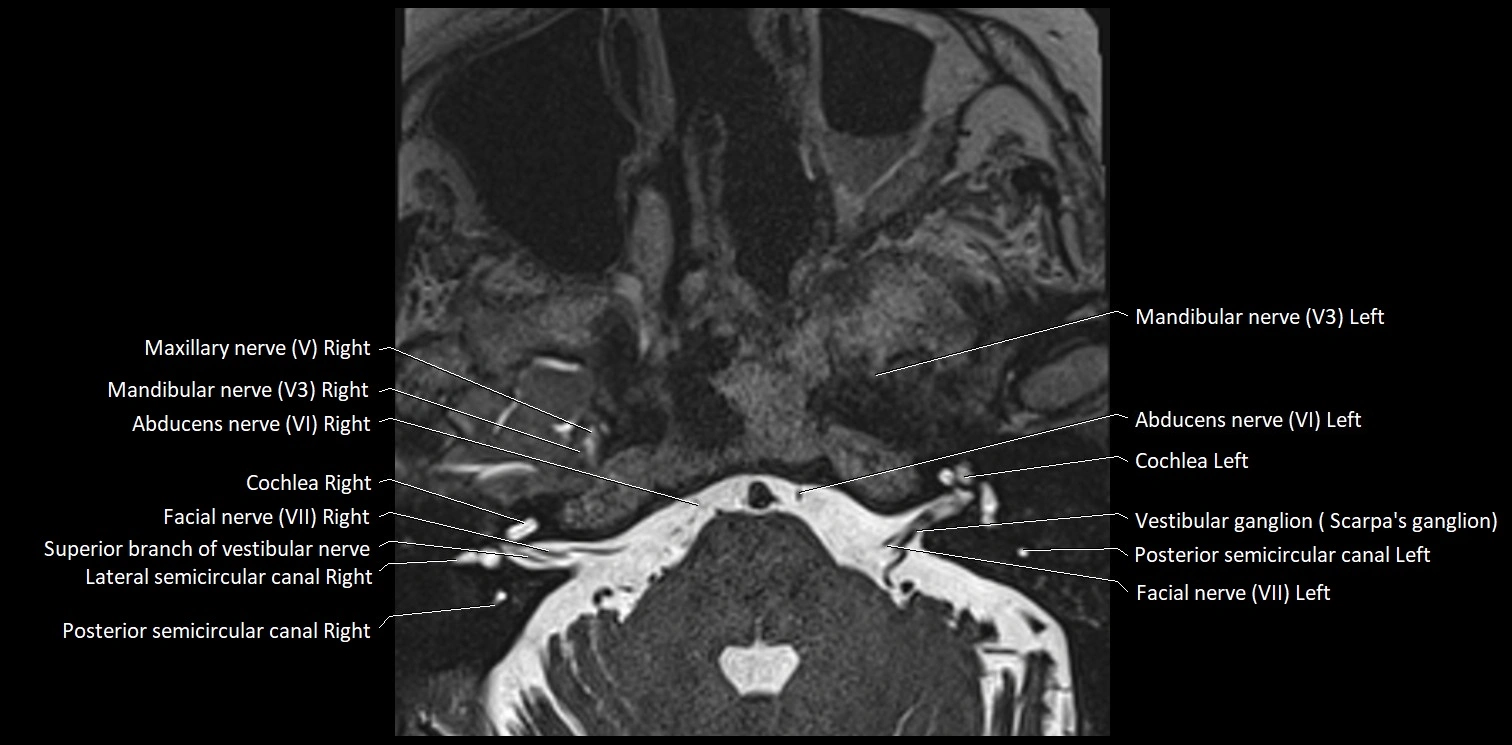

MRI Appearance

• The abducens nerve is a small, thin, linear structure

• Best visualized on high-resolution T2-weighted 3D MRI sequences (e.g., FIESTA or CISS)

• Seen as a hypointense (dark) line running from the brainstem at the pontomedullary junction, traversing the prepontine cistern, and entering Dorello’s canal under the petrosphenoidal ligament, then into the cavernous sinus, and finally the orbit

• May be challenging to visualize in standard MRI due to its small size

• Pathology may be inferred by absence, displacement, or enhancement of the nerve